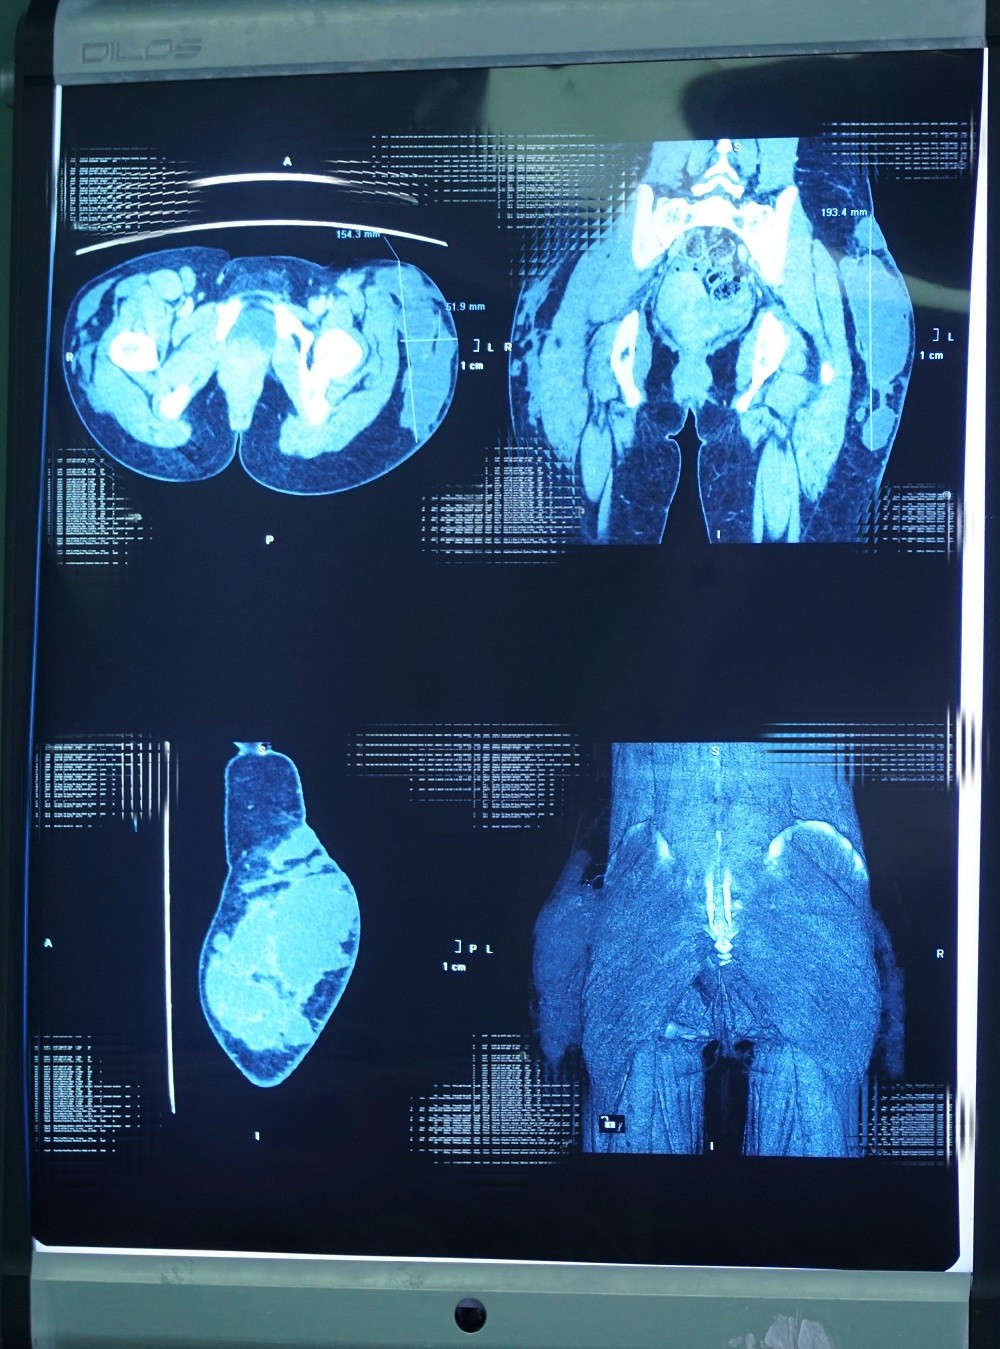

Khi cơn đau ngày một dữ dội, chị gần như không thể ngồi hay đi lại. Hình ảnh chụp MRI cho thấy, bên trong là khối áp xe khổng lồ dài hơn 20cm, dày 15cm, lan rộng xuống cơ, tạo thành các hốc chứa dịch viêm như “tổ ong”.

TS.BS Nguyễn Phan Tú Dung cho biết, đây là trường hợp nghiêm trọng, ổ áp xe đã ăn sâu vào các mô cơ tạo thành cấu trúc tổ ong, có nguy cơ lan rộng gây nhiễm trùng huyết nguy hiểm tính mạng nên đã yêu cầu mổ khẩn cấp.